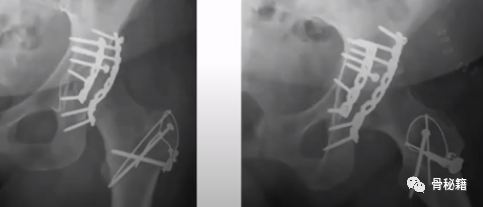

4、大粗隆骨折